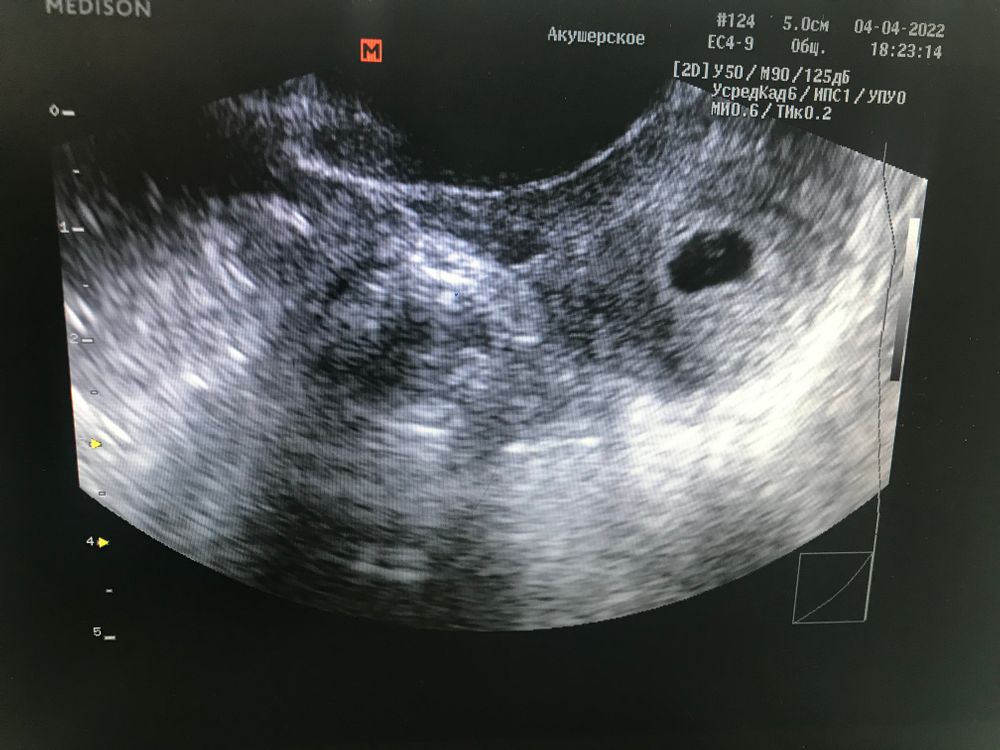

Алёна, я сходила на узи сегодня) Изображение

Наташа , слава богу все хорошо 🤞

Алёна, Врач сказала- да) я немного успокоилась)